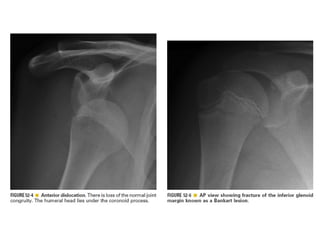

Skeletal trauma was presented by Dr Laith Fadhel with reference to Grainger's Diagnostic Radiology textbook. The presentation covered skeletal trauma as assessed through diagnostic radiology techniques. Key findings and treatments for skeletal injuries were likely discussed.